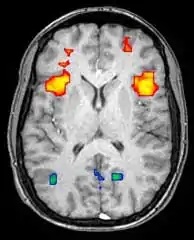

Axial MRI slice at the level of the basal ganglia, showing fMRI BOLD signal changes overlaid in red (increase) and blue (decrease) tones

Functional magnetic resonance imaging (fMRI) and arterial spin labeling (ASL) relies on the paramagnetic properties of oxygenated and deoxygenated hemoglobin to see images of changing blood flow in the brain associated with neural activity. This allows images to be generated that reflect which brain structures are activated (and how) during the performance of different tasks or at resting state. According to the oxygenation hypothesis, changes in oxygen usage in regional cerebral blood flow during cognitive or behavioral activity can be associated with the regional neurons as being directly related to the cognitive or behavioral tasks being attended.

Most fMRI scanners allow subjects to be presented with different visual images, sounds and touch stimuli, and to make different actions such as pressing a button or moving a joystick. Consequently, fMRI can be used to reveal brain structures and processes associated with perception, thought and action. The resolution of fMRI is about 2-3 millimeters at present, limited by the spatial spread of the hemodynamic response to neural activity. It has largely superseded PET for the study of brain activation patterns. PET, however, retains the significant advantage of being able to identify specific brain receptors (or transporters) associated with particular neurotransmitters through its ability to image radiolabeled receptor "ligands" (receptor ligands are any chemicals that stick to receptors). There is also significant concern regarding the validity of some of the statistics used in fMRI analyses; hence, the validity of conclusions drawn from many fMRI studies.[22]